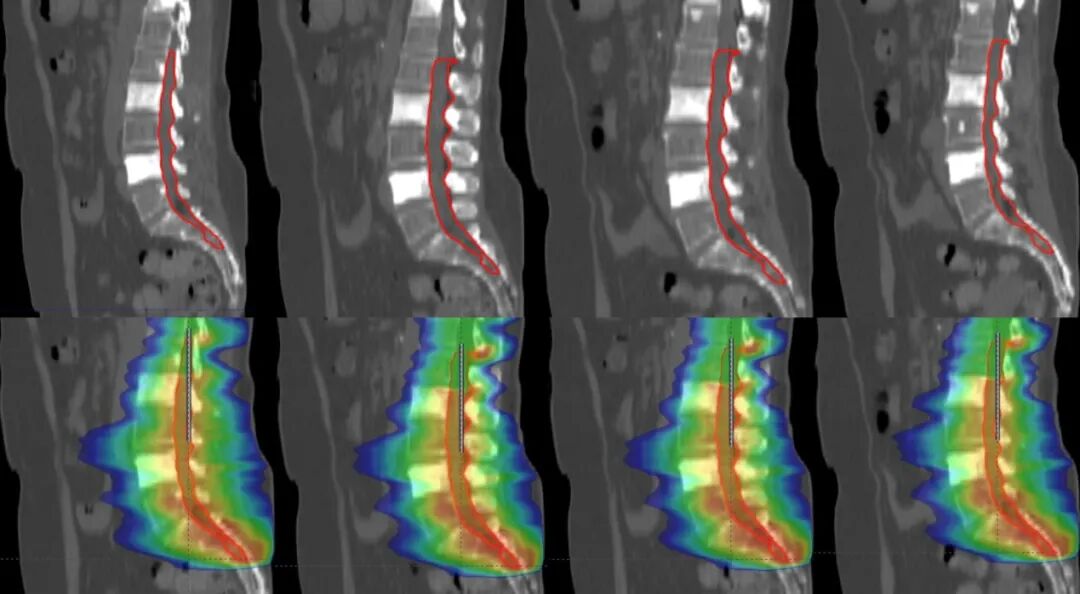

【學科風采】乳腺癌患者千里求醫(yī),成功治療多發(fā)腦轉移瘤、脊髓轉移、腦膜轉移、椎管內多發(fā)轉移結節(jié)、肺炎及肺門轉移患者